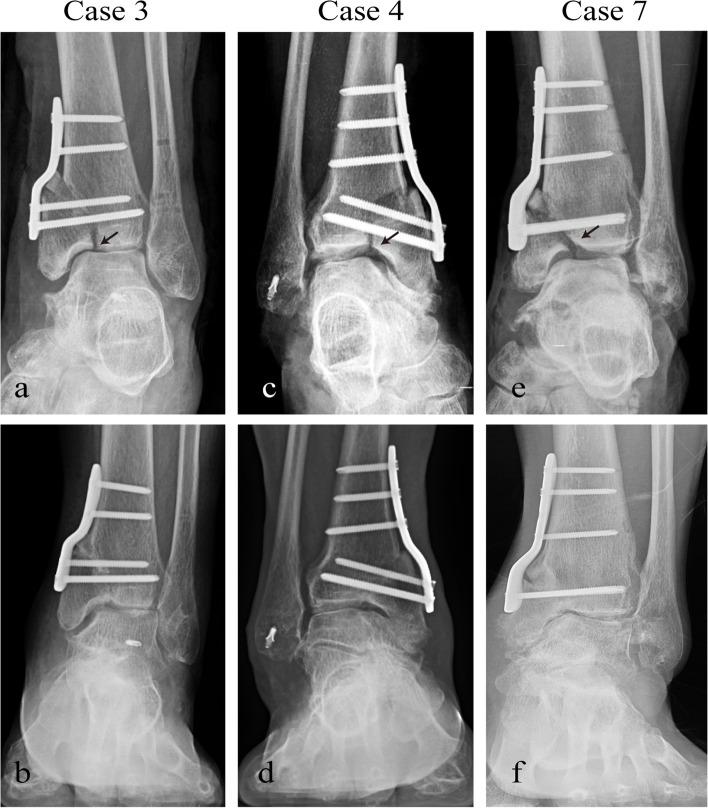

Nineteen patients with intra-articular varus ankle arthritis were reviewed between April 2017 and June 2019, including ten men and nine women with a mean age of 58.3 ± 9.9 years (range, 38 to 76 years). All patients underwent intra-articular opening wedge osteotomy assisted by 3D virtual planning and PSI. Weight-bearing radiographs were used to assess the radiographic results, including TAS angle, TT angle, TMM angle, TC angle, TLS angle, opening-wedge angle, and wedge height. Functional outcomes were assessed by the AOFAS score, VAS score, and ROM of the ankle.

RESULTS

The average follow-up time was 32.2 ± 9.0 months (range, 22 to 47 months). The average union time was 4.4 ± 0.9 months (range, 3.0 to 6.5 months). The TAS angle significantly changed from 84.1 ± 4.6° preoperatively to 87.7 ± 3.1° at the 1-year follow-up and 86.2 ± 2.6° at the latest follow-up. Similarly, the TT angle, TMM angle and TC angle changed significantly at the 1-year follow-up compared with the preoperative assessment and remained stable until the last follow-up. However, the TLS was not corrected significantly. The postoperative obtained opening-wedge angle, and wedge height showed no significant change with preoperative planning. The overall complication rate was 15.8%. The mean VAS score improved from 5.3 ± 0.6 to 2.7 ± 0.7. The mean AOFAS score improved from 56.2 ± 7.6 to 80.6 ± 4.6. However, the ROM showed no significant change.